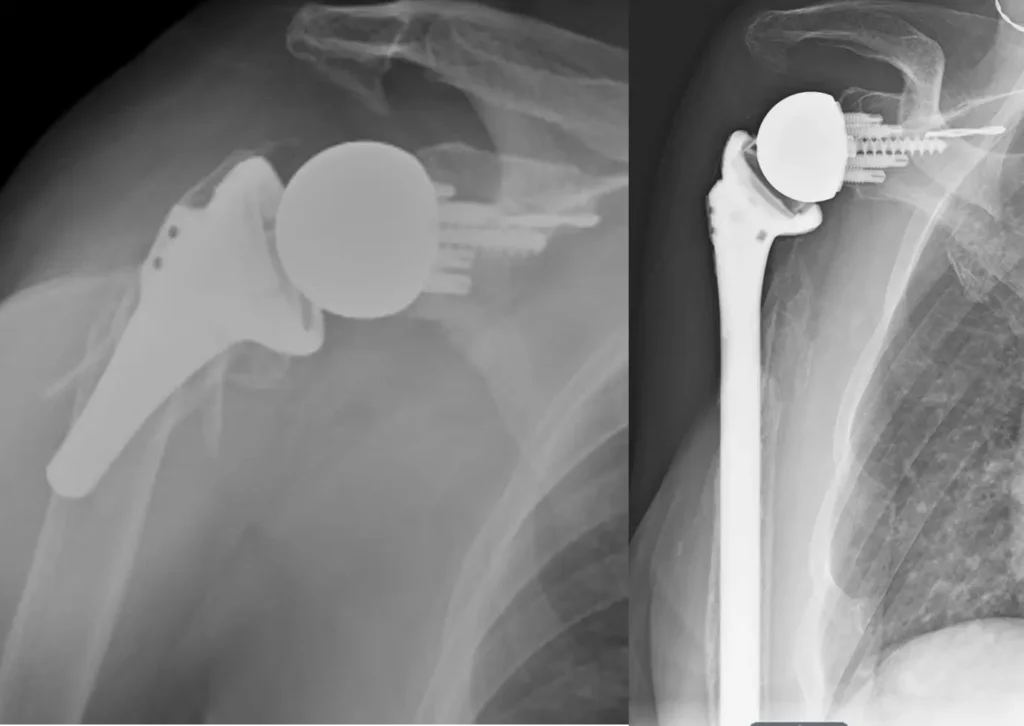

Combined surgical fixation acetabulum and total hip for geriatric acetabulum fracture

Combined surgical fixation acetabulum and total hip for geriatric acetabulum fracture